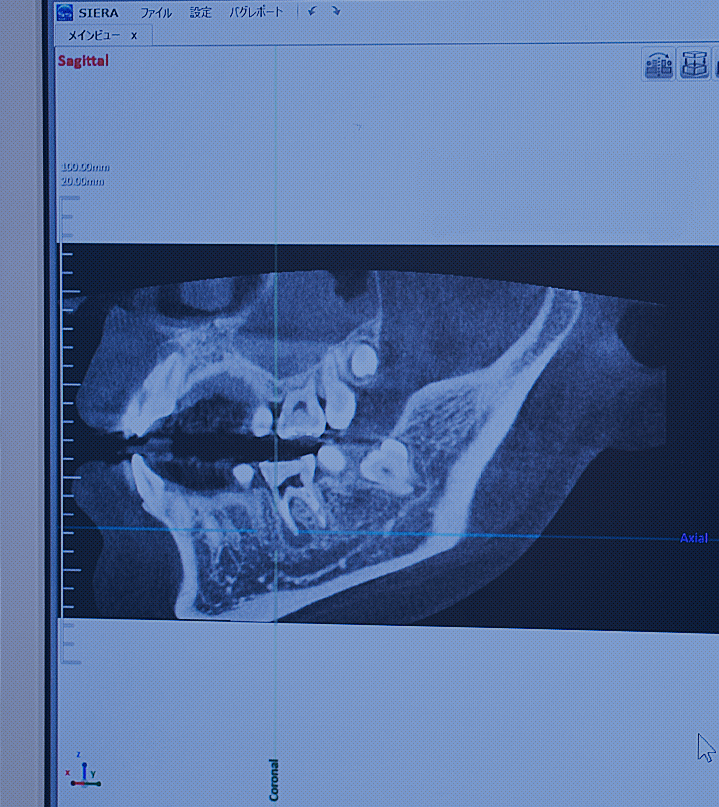

CTを用いることで、最薄0.076mmの断層撮影、3D撮影が可能なため従来の撮影機よりも詳細に患者様の状態をお調べし診断することが可能となりました。

インプラント治療は、骨の状態により切ってから手術を中止することになったり、うまくインプラントを埋入できずに再手術を行うこともありますが、CTで事前検査を行うことでそのリスクを減らした手術を行うことが可能になります。

部位ごとの撮影も可能で、従来のものよりも照射時間が短いためお身体への負担も少ないのが特長です。

通常のレントゲンでは見ることが出来なかった骨の厚みをより詳細に調べることができるため、必要最小限の治療で患者様の負担を軽減することが可能となりました。